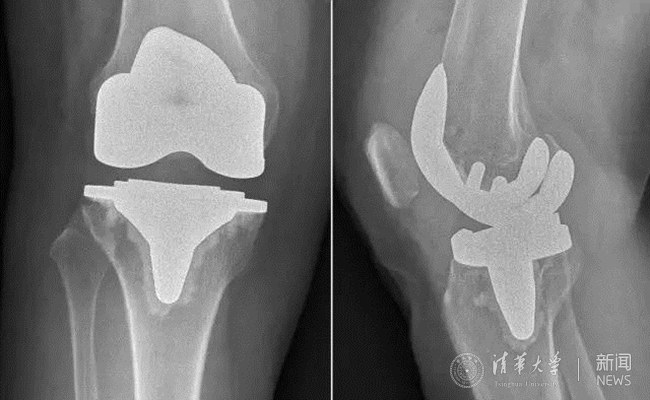

结合患者的实际情况及诉求,蔡谞教授带领骨科团队决定运用最新引进的关节假体。据蔡谞教授介绍,该新型假体在假体形态上采用渐变半径,使病人在屈膝的全过程平滑稳定固定,改良的滑车设计优化了髌骨轨迹,全新的凸轮设计在保证稳定性的同时,将传导到垫片立柱的压力最小化,而中央锁定胫骨平台,优化了固定平台的运动学特性,将背部微动降到最低,能够最大限度改善患者的生活质量。

患者术后膝关节平片。

疗效改善的同时,新型假体对手术精准度的要求也提高了,为此,蔡谞教授和关节中心团队做了充足的准备,术前对手术参与人员进行了严格的操作训练。手术全程1个小时左右顺利结束,术后影像显示,新型假体安放位置精确,患者术后第2天即开始下床进行功能锻炼,术后7天顺利出院。